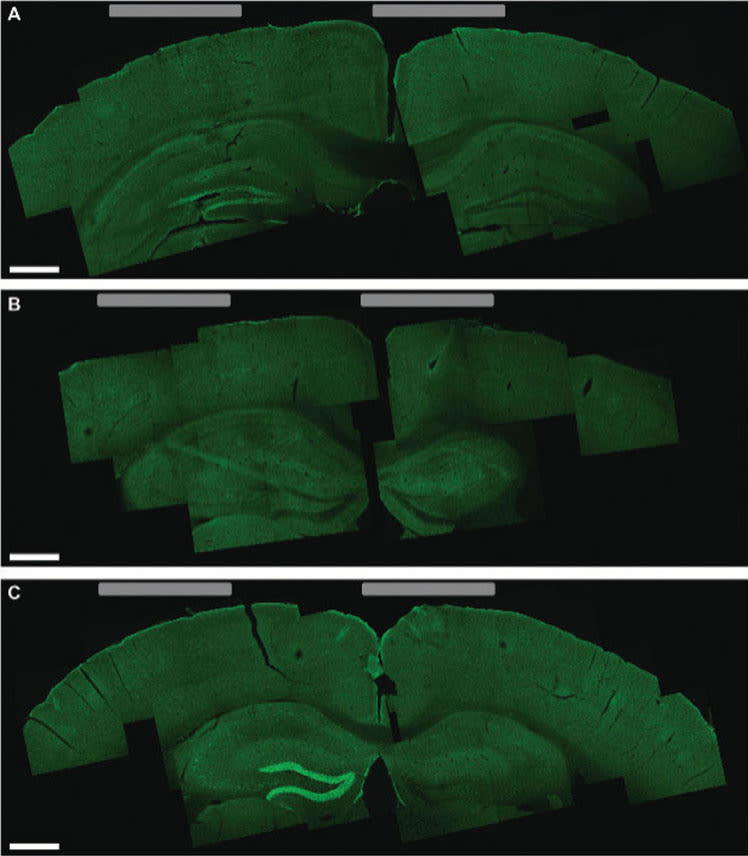

Li-Huei Tsai, director of MIT’s Picower Institute for Learning and Memory, and researchers in her lab tested this technique in mice and found that they could stimulate small regions deep within the brain, including the hippocampus. They were also able to shift the site of stimulation, allowing them to activate different parts of the motor cortex and prompt the mice to move their limbs, ears, or whiskers.

“We showed that we can very precisely target a brain region to elicit not just neuronal activation but behavioral responses,” says Tsai, who is an author of the paper. “I think it’s very exciting because Parkinson’s disease and other movement disorders seem to originate from a very particular region of the brain, and if you can target that, you have the potential to reverse it.”

Significantly, in the hippocampus experiments, the technique did not activate the neurons in the cortex, the region lying between the electrodes on the skull and the target deep inside the brain. The researchers also found no harmful effects in any part of the brain.